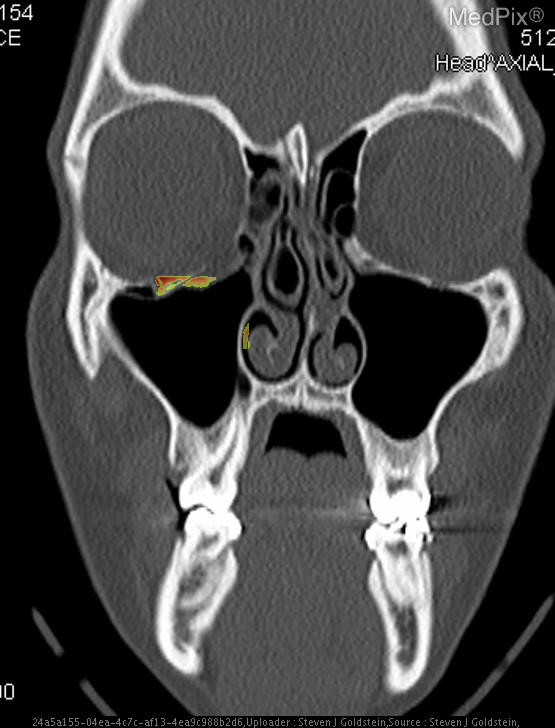

- Coronal CT image shows discontinuity of the orbital floor on the image-left (patient-right) side.

- Herniation of orbital fat and partial inferior displacement of soft tissue into the maxillary sinus on the image-left (patient-right).

- Air-fluid level within the right maxillary sinus (image-left side), consistent with hemorrhage or fluid collection.

- Intact orbital floor on the image-right (patient-left) side.

- Globes are intact bilaterally, without evidence of rupture or significant intraorbital hematoma.

- Nasal septum roughly midline; ethmoid air cells and remaining paranasal sinuses are clear.

Orbital floor (blowout) fracture on the image-left (patient-right) side. The CT demonstrates a defect in the orbital floor with herniation of orbital contents into the maxillary sinus, a classic feature of a blowout fracture. The presence of sinus fluid and continuity of orbital fat confirms disruption of the orbital floor. Context consistency: Consistent. Context title and imaging findings are in agreement for an orbital floor fracture. Confidence: 95%.